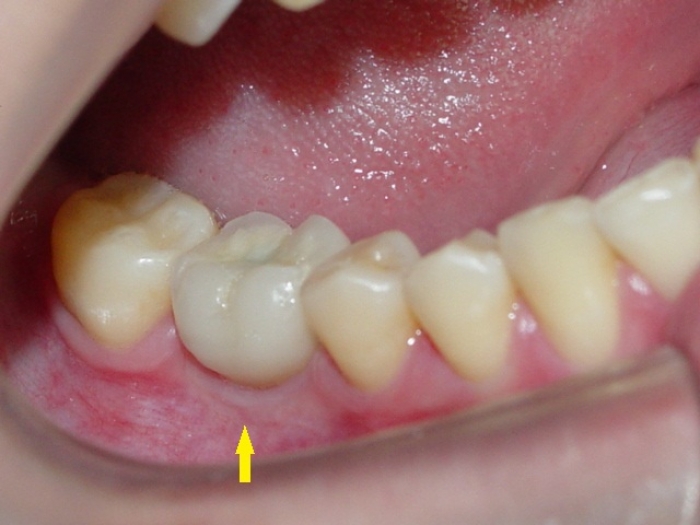

Imagens da prótese unitária sobre implante, do caso finalizado em janeiro de 2011